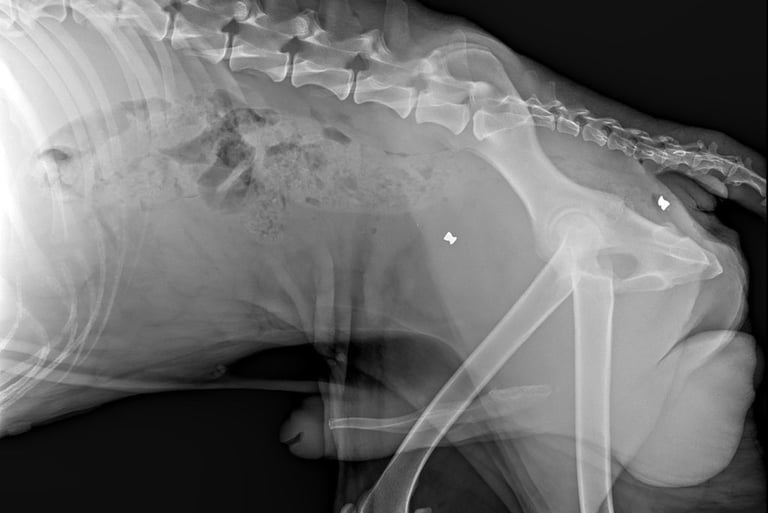

Cooper’s story is heartbreaking. He was found near the woods in Hilliard, painfully thin and carrying the scars of a cruel past. X-rays revealed he had been shot with BB guns, and four pellets are still lodged in his body.